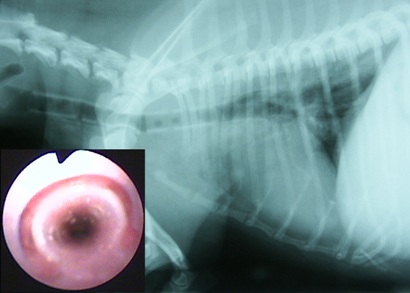

診断 気管虚脱GradeIV

処置および経過:Tチューブ(8mm)留置し救急処置(図14)。Vet Stent-Tracheaに交換(図15)

合併症:なし(図16)。現在follow中(267日間)。

図14 症例3の初診日、Tチューブ留置。

図15 症例3の第79病日Vet Stent-Tracheaに交換。

図16 症例3の第243病日の気管支鏡所見。Vet Stent-Tracheaを留置後6ヶ月経過するが肉芽形成、細菌感染は全くみられない。